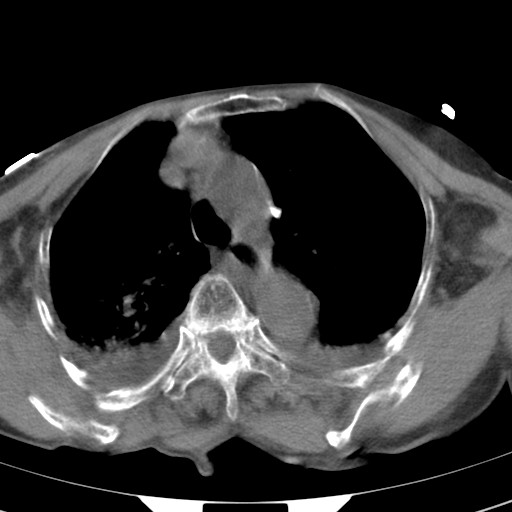

女,93岁,摔伤后检查。

右肺炎症,心功能不全伴双侧胸腔积液,右下肺膨胀不全,食管裂孔疝,冠脉钙化,心包少量积液,左侧肋骨骨折,请上传骨窗.

右侧锁骨\\肩胛骨骨折、右侧湿肺,心功能不全伴双侧胸腔积液,右下肺膨胀不全,左膈破裂或食管裂孔疝,冠脉钙化,心包少量积液,请上传骨窗.

右肺炎症,心功能不全伴双侧胸腔积液,右下肺膨胀不全,食管裂孔疝,冠脉钙化,心包少量积液,左侧肋骨骨折,右肩甲骨粉碎性骨折。93岁,高寿哇!

右肺炎症,心功能不全伴双侧胸腔积液,右下肺膨胀不全,食管裂孔疝,冠脉钙化,心包少量积液,左侧肋骨骨折,右肩甲骨粉碎性骨折。